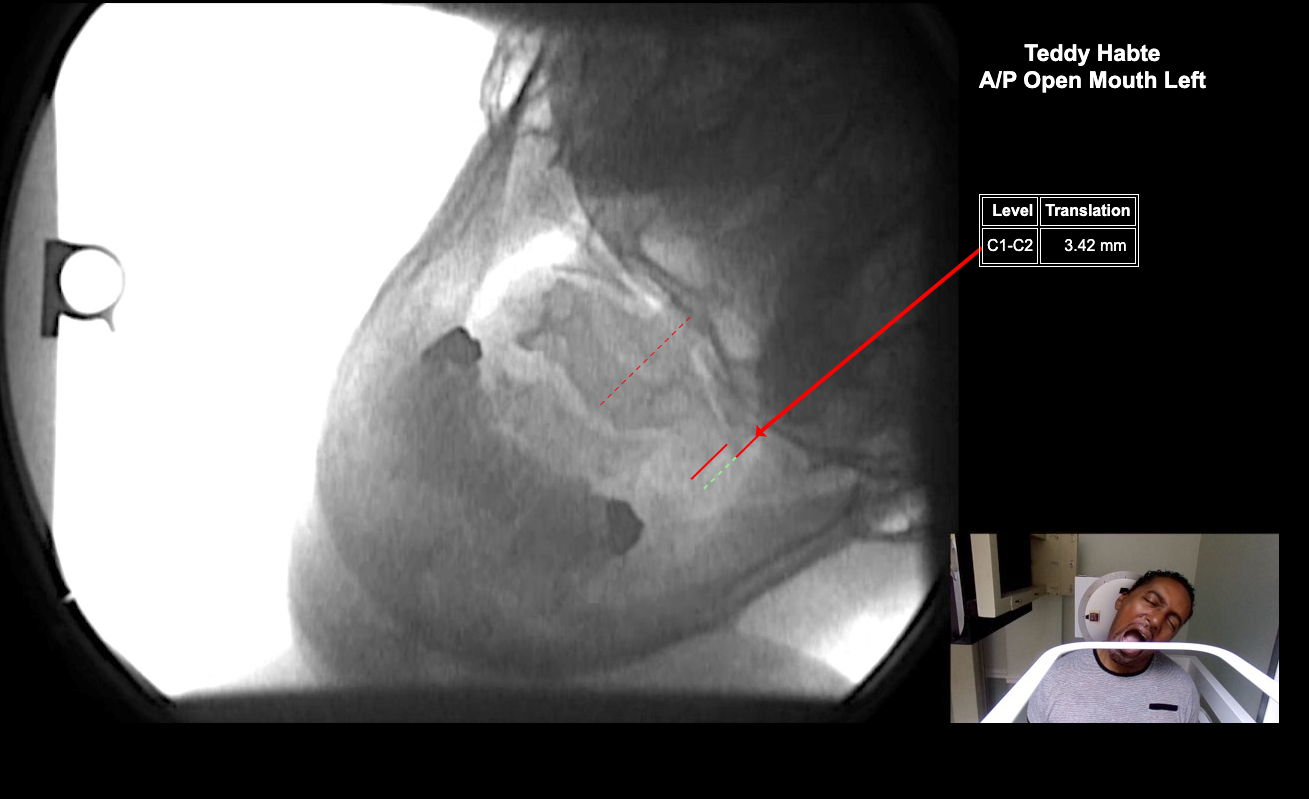

Home > Teddy Habte 6-24-25

Image 2